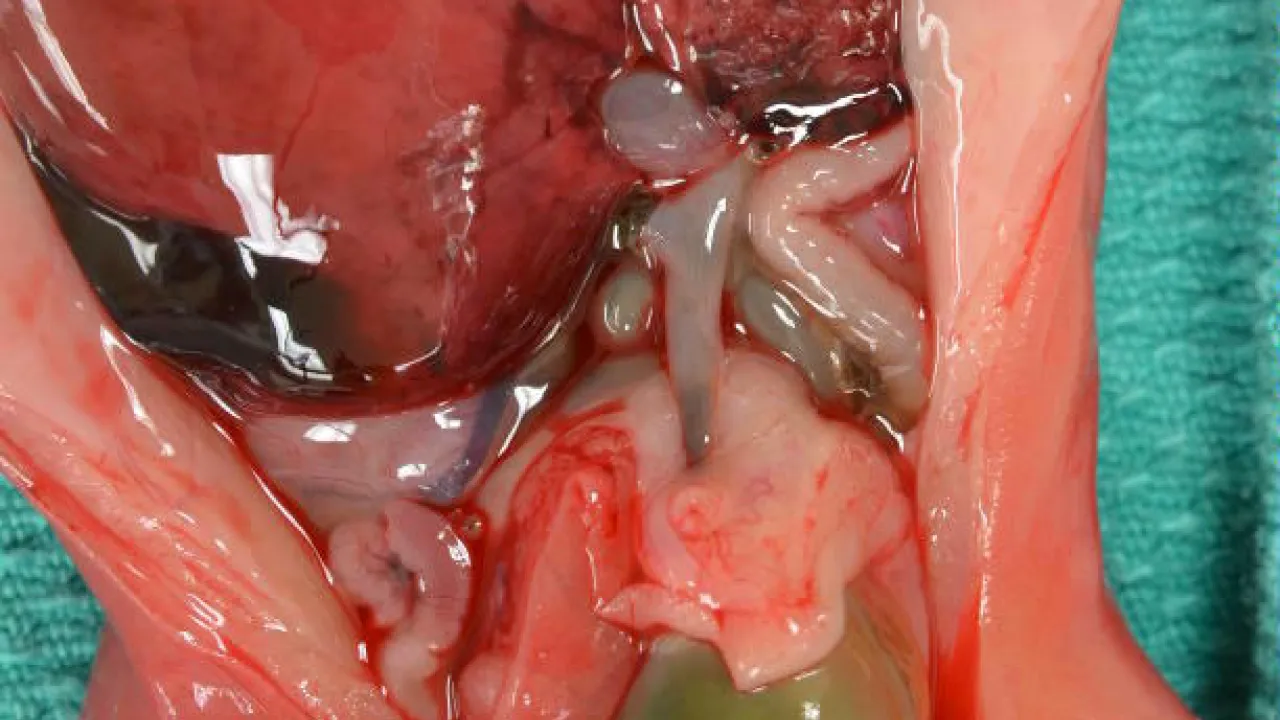

Lower Urinary Tract and Male Genital System